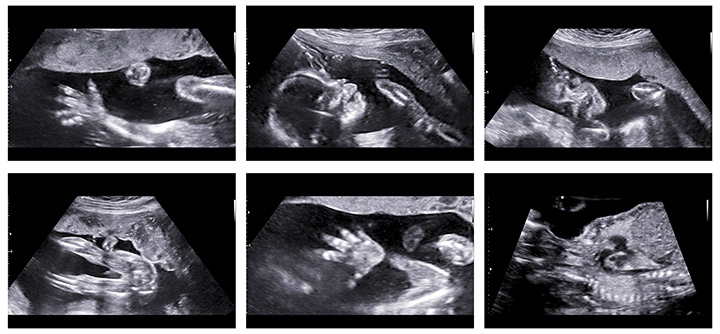

آزمایش غربالگری سه ماه دوم بارداری شامل یک آزمایش خون از مادر باردار به همراه یک سونوگرافی است که به آن سونوگرافی آنومالی یا تفصیلی میگویند. آزمایش خون همان طور که گفته شد به منظور اندازه گیری چهار ماده در خون مادر انجام میشود. سونوگرافی آنومالی نیز در هفته ۱۶ تا ۱۸ بارداری انجام شده و به بررسی وضعیت رشد جنین و وجود هر گونه ناهنجاری در آناتومی جنین از جمله ساختار ستون فقرات، قلب، صورت و اعضای دیگر بدن میپردازد. همچنین لب شکری بودن جنین نیز با این سونوگرافی تشخیص داده میشود.